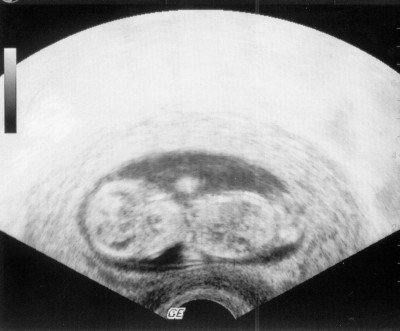

Ich habe heute am Rande mitbekommen, dass die Paare für die künstliche Befruchtun künftig keinen Trauschein mehr benötigen ?

Endlich !!!!!!!